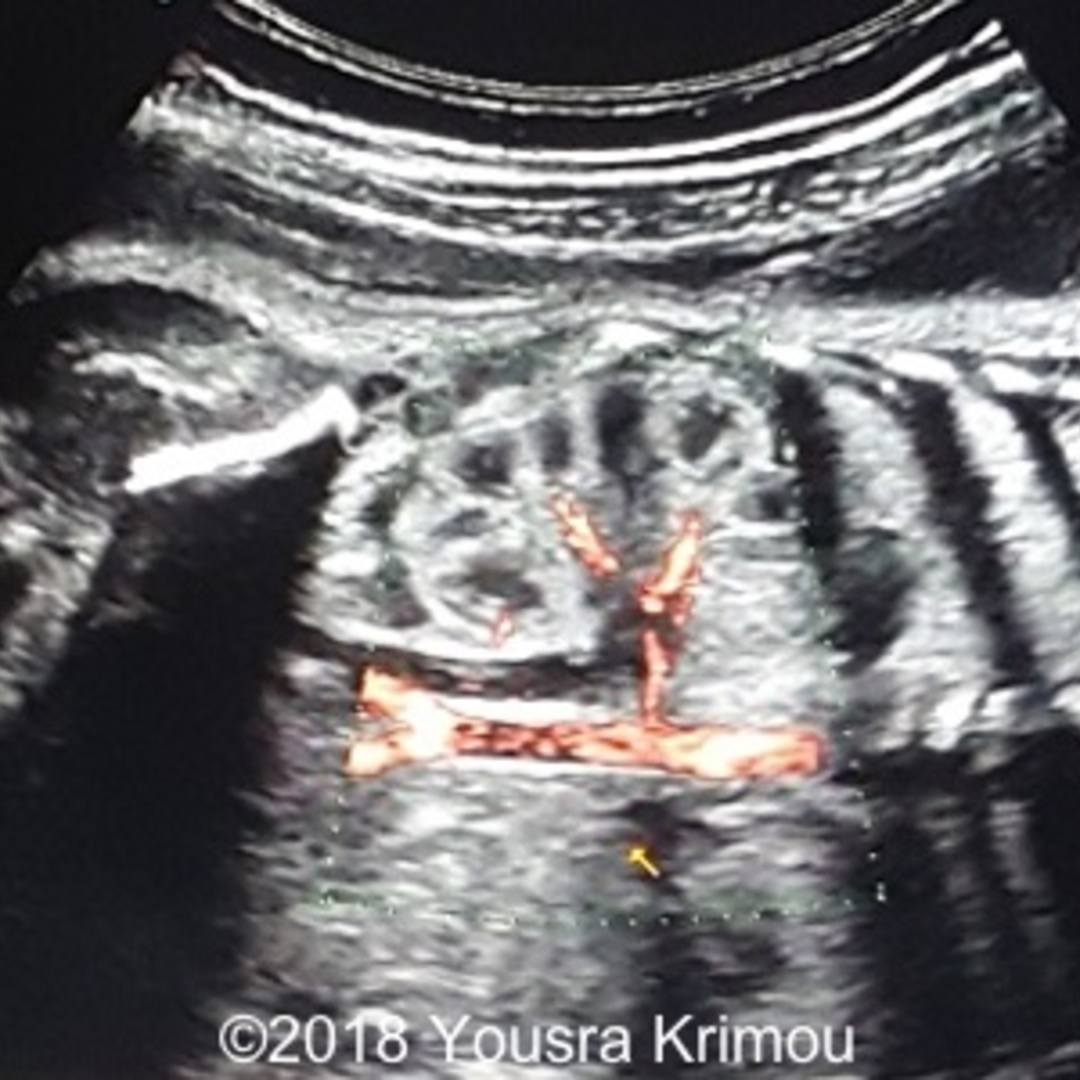

From ultrasound-videos.blogspot.com

Ultrasound and Color Doppler videos Pelvic kidney ultrasound video study Fused Pelvic Kidney Ultrasound ultrasonography gives useful information on the morphology and. four types of crossed renal ectopia (fig 14) can be seen at imaging, mainly at ct and mri, including cre with fusion characterized by the ectopic kidney crossing over to the opposite side, with its upper pole fused to the lower pole of the normal kidney and its ureter crossing. Fused Pelvic Kidney Ultrasound.